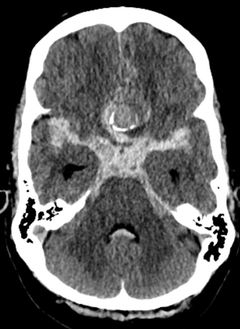

The researchers examined the quality of the treatment of unruptured intracranial aneurysms. In the study, 169 consecutive patients who were treated at HUS either with microsurgery (29% of patients) or endovascular therapy (71%) between December 2022 and August 2024 were included.

Although the patients’ functional outcome was excellent, the sensitive MRI diffusion-weighted images (DWI) revealed new, small ischemic lesions, i.e. changes caused by lack of oxygen or microthrombosis, in 63% of the patients. Most of these were asymptomatic, but they were associated with an increased risk of developing new transient neurological symptoms. The result shows that the traditional indicators of functional outcome, in other words the mRS, do not reveal all the effects that the treatment has on the brain.